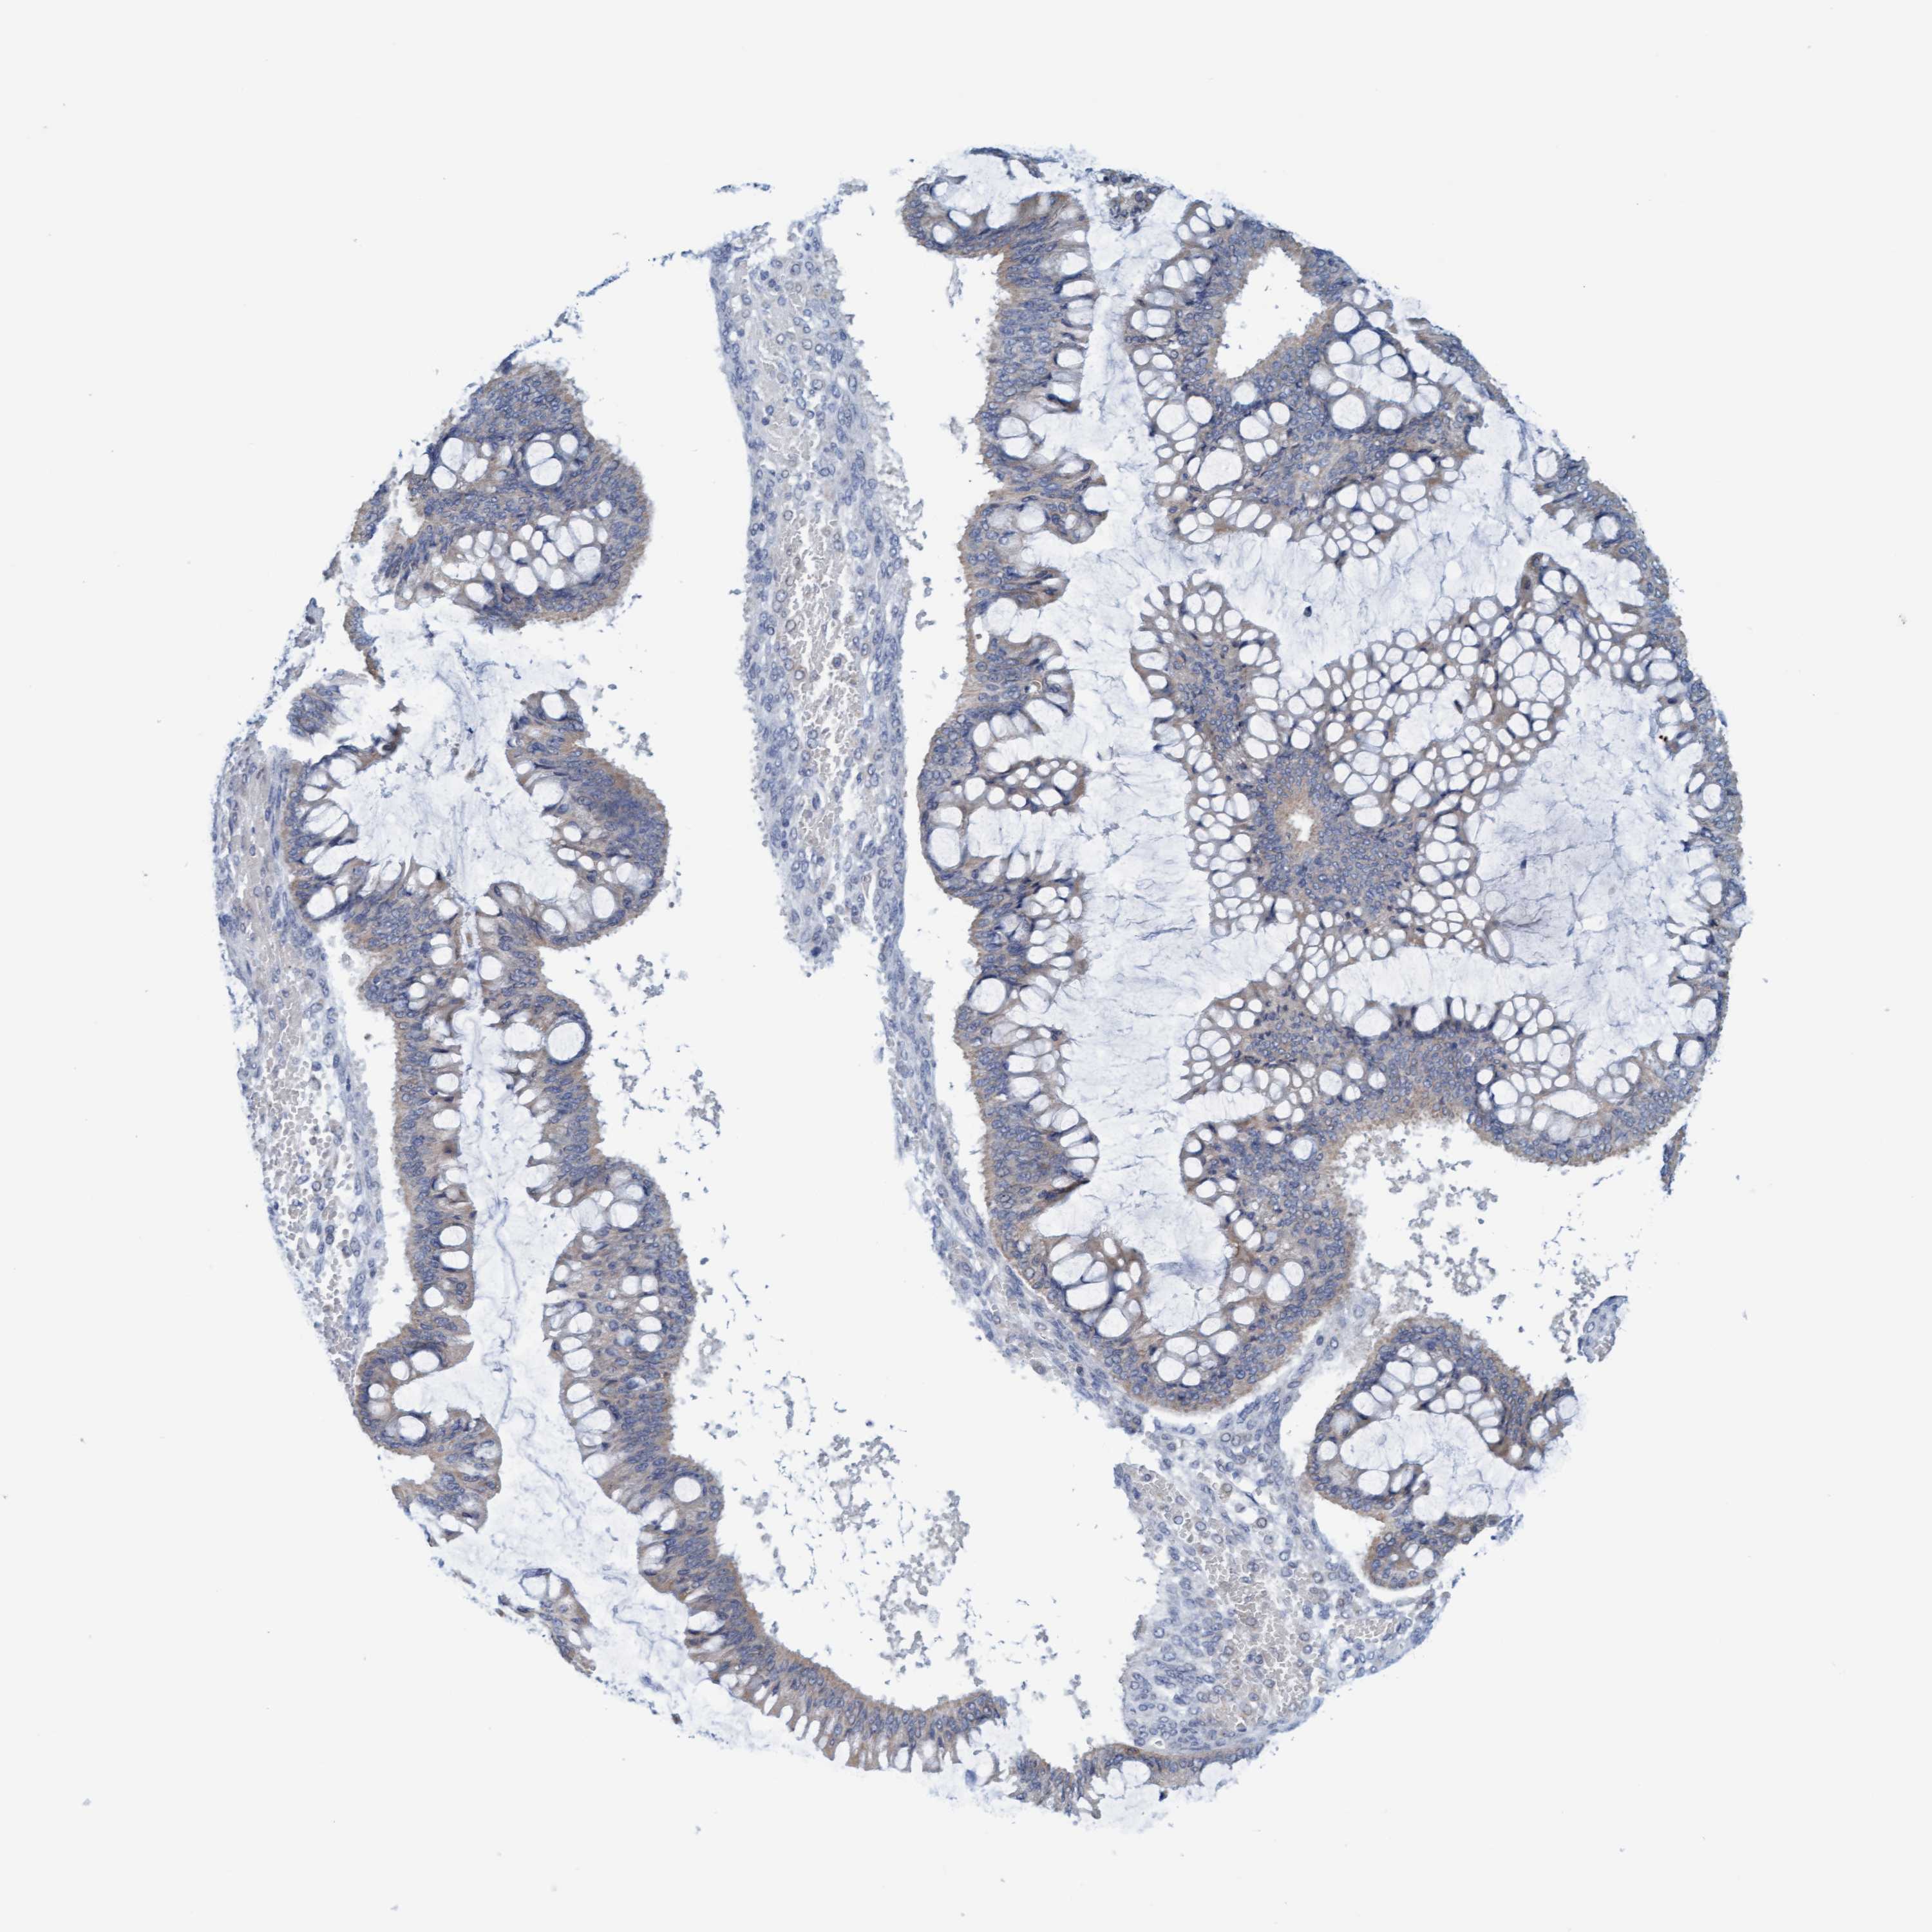

OVARIAN CANCER - Protein expressioni

A mouse-over function shows sample information and annotation data. Click on an image to view it in a full screen mode. Samples can be filtered based on level of antibody staining by selecting one or several of the following categories: high, medium, low and not detected. The assay and annotation is described here.

Note that samples used for immunohistochemistry by the Human Protein Atlas do not correspond to samples in the TCGA dataset.

Antibody stainingi

Antibody staining in the annotated cell types in the current human tissue is reported as not detected, low, medium, or high, based on conventional immunohistochemistry profiling in selected tissues. This score is based on the combination of the staining intensity and fraction of stained cells.

Each image is clickable and will lead to virtual microscopy that enables deeper exploration of all samples and also displays staining intensity scores, fraction scores and subcellular localization as well as patient and tissue information for each sample.

Antibody HPA006479

Antibody HPA008689

Antibody CAB020712

Cystadenocarcinoma, serous, NOS